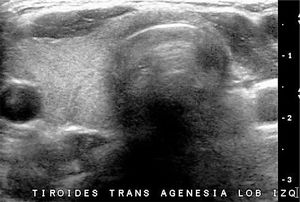

La ausencia del tiroides, grado máximo de las disgenesias tiroideas, es raro y el diagnóstico de no ser muy temprano causa estragos en el desarrollo neurológico del paciente. En los casos en que el tiroides no está en su ubicación habitual y el paciente no tiene historia de hipotiroidismo neonatal, la sospecha clínica se orienta a presencia de tejido tiroideo de ubicación ectópica, que puede reemplazar la función del órgano normal, aunque tarde o temprano será insuficiente. La exploración ecográfica deberá incluir el trayecto descendente del tiroides embrionario, desde la base de la lengua hasta su ubicación habitual. La hemiagenesia o hemiagénesis del tiroides también es poco frecuente y es difícil de determinar su verdadera frecuencia, ya que la mayoría de las veces el paciente tiene función conservada y por tanto, no se realiza estudio de imágenes tiroideas. La mayoría corresponden a hemiagenesias del lóbulo izquierdo con o sin agenesia del istmo (Figura 4).